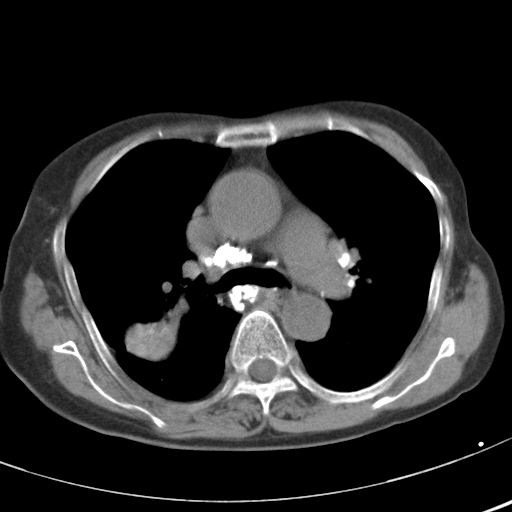

以下是引用hhcckk在2007-3-2 14:51:00的发言:[br]考虑结核球可能性大,依据[br]1病灶在下叶背段,结核的好发部位[br]2病灶内有大量的钙化,纵隔内有大量的淋巴结钙化[br]3重要的是半年前与现在相比无变化,假如是肿瘤的话不会这么‘善良’[br]4病灶周围卫星灶不明显,病灶有毛刺,胸膜凹陷,肿瘤不能完全排除,有条件的话最好做个活检

以下是引用liuyue在2007-3-2 17:15:00的发言:[br]1位置:右上叶后段[br]2性质:大分叶、粗长毛刺、条状斑片状钙化、纵隔多发淋巴结钙化,无强化,故考虑:肺结核灶(陈旧)